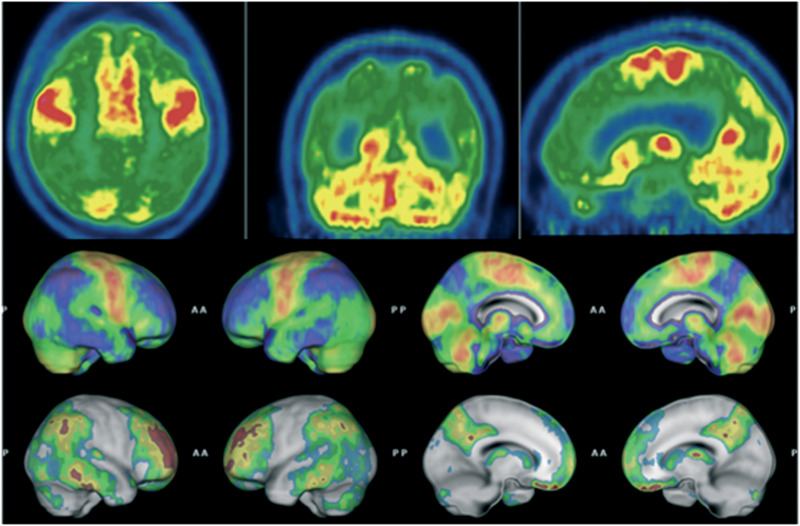

Abstract Image